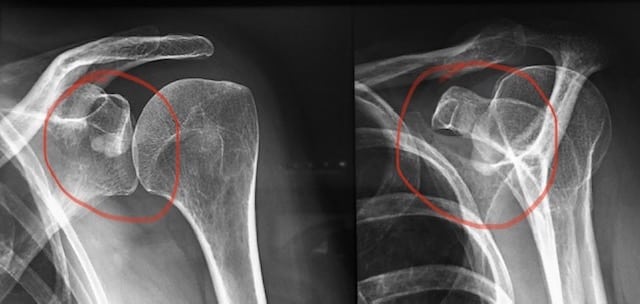

Luxation antérieure

Vue articulaire

Le traitement préconisé en cas de luxation, subluxation et instabilité, est la rééducation. Elle permet d’améliorer la stabilité et de supprimer la douleur. Si malgré la rééducation les luxations deviennent récidivantes, les subluxations trop gênantes et l’épaule instable, trop douloureuse ou invalidante, limitant les activités et gênant la qualité de vie, un bilan s’impose et une chirurgie peut être proposée. Un bilan radiographique complété d’un scanner, ou d’une IRM, et couplé à une injection de produit de contraste permet d’identifier les lésions de l’os (glène ou tête humérale) et de mettre en évidence une fissure du bourrelet, ou un arrachement des ligaments.Un bilan radiographique complété d’un scanner ou d’une IRM et couplé à une injection de produit de contraste permet d’identifier les lésions de l’os (glène ou tête humérale) et de mettre en évidence une fissure du bourrelet, ou un arrachement des ligaments.